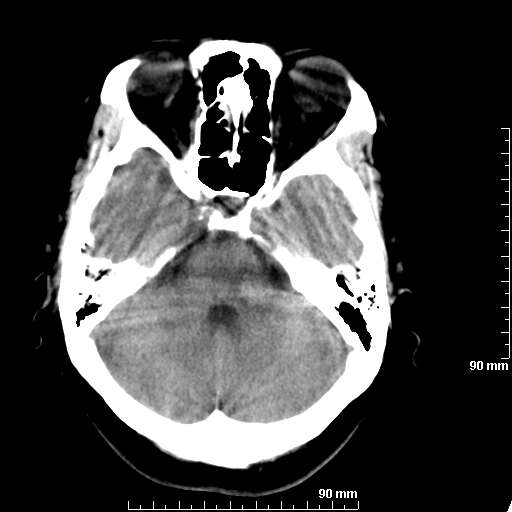

[维修案例解析] 大家猜猜看,这个伪影是怎样产生的.

二马日王 显示全部楼层 发表于 2011-6-9 18:12:55 |阅读模式

我院西门子单排CT由于一零件受损而产生的伪影.

哈哈,都不是。是虑线器fiter裂损。大家没想到吧。

哦,跟脑出血有点像哦

形状不规则,边缘模糊。比较特殊的一种伪影哈!

这种伪影很常见!伪影应该是在视野的中心的。

西门子的虑线器fiter裂损这才是很难见的问题,GE的最常见

虑线器老化,中间崩裂一块掉了

确实是虑线器,但是很少见

确实是虑线器,听说过,赞一个